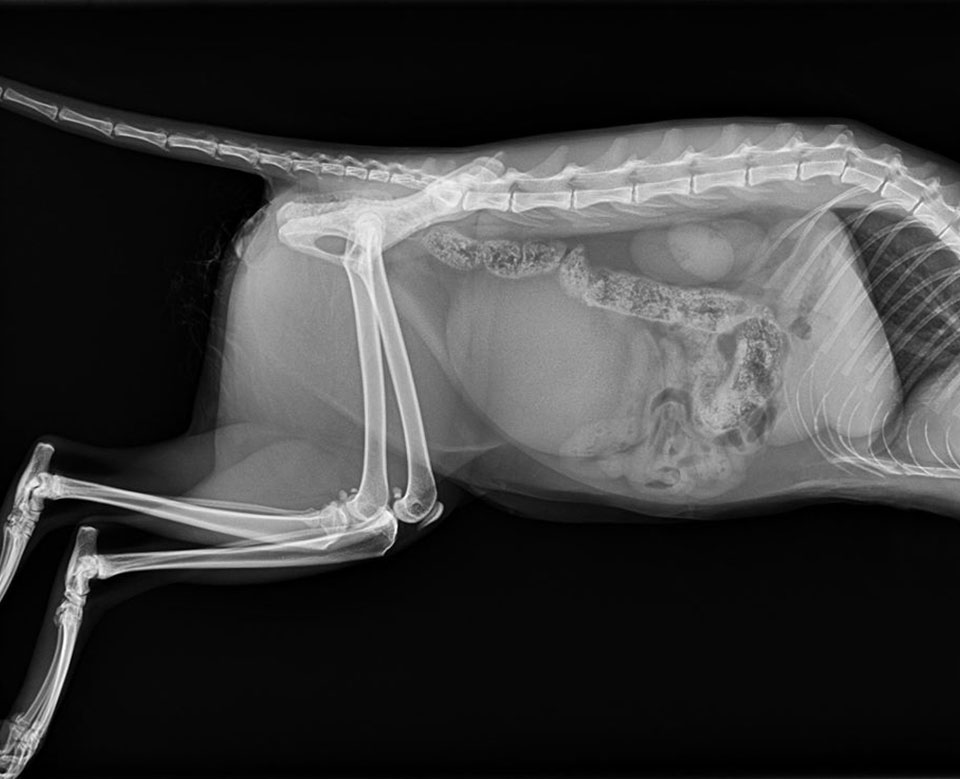

Mini SOP-LC (for 2,0mm srews) were used for stabilisation of vertebral luxation and fracture in cat.